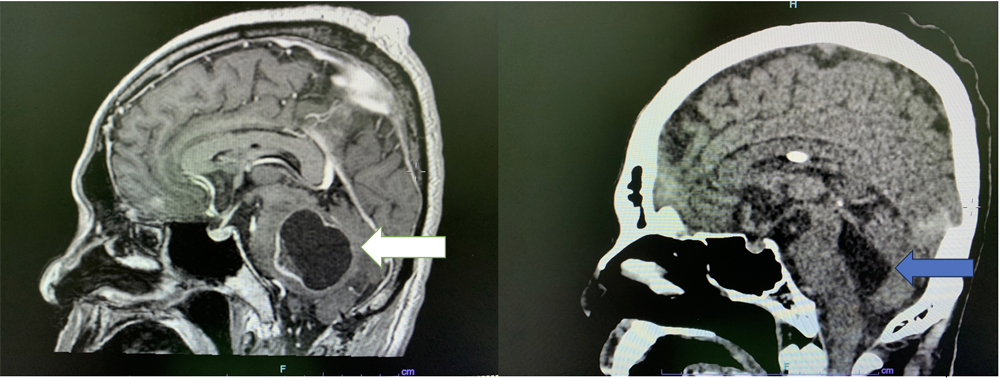

阿宏的肿瘤就长在右脑桥,右脑桥肿瘤(Cerebro pontine tumour)属良性肿瘤,但因为肿瘤太大,压迫脑神经,造成脑压升高,导致听觉受损、频密头痛和步伐不稳等。

去年6月,阿宏在一家私人医院接受手术,切除肿瘤,但由于位置深入颅底窝且广泛生长,医生只成功切除70~80%的肿瘤。

5个月后,阿宏再接受俗称“电脑刀”的放射治疗,杀死残余的肿瘤细胞。“电脑刀”对实体肿瘤有效,对囊性肿瘤却束手无策,治疗后,实体肿瘤有缩小,但囊性肿瘤却出现水肿和扩大的现象,压制神经中枢,令阿宏的头痛再次发作,手脚抽搐,身体虚弱得只能躺在床上。

由于阿宏已经无法再做手术,所以医生只能在他的头皮下置入储液器排气阀(Reservoir aspiration valve),方便医护人员抽出脑肿瘤囊腔积液(Brain tumour cystic cavity fluid),给颅内减压。

我在电脑导航的帮助下,从阿宏的头颅抽出了20cc的积液,颅内压降下来后,他的精神明显好多了,吞咽也比较有力,手脚抽搐也大有改善。